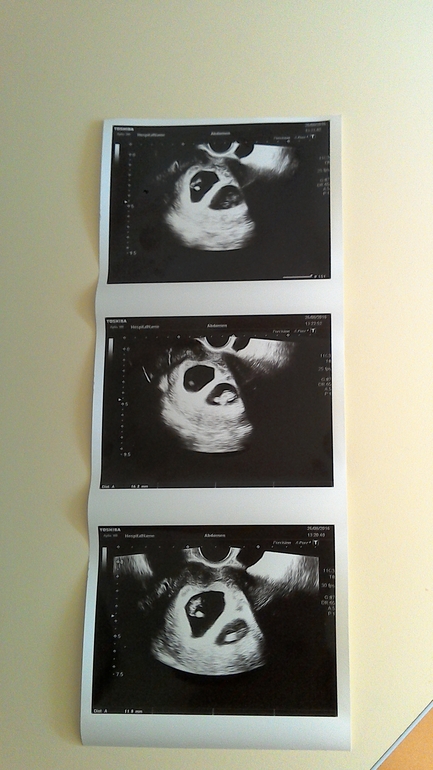

7 недель УЗИ

Мы растем! Первый малыш 16 мм, второй 12.

Первое фота братика и сестрички, мы еще очень маленькие, но сердечки бьются.

Ага, сама прям пол дня рассматривала где пузики, а где головки